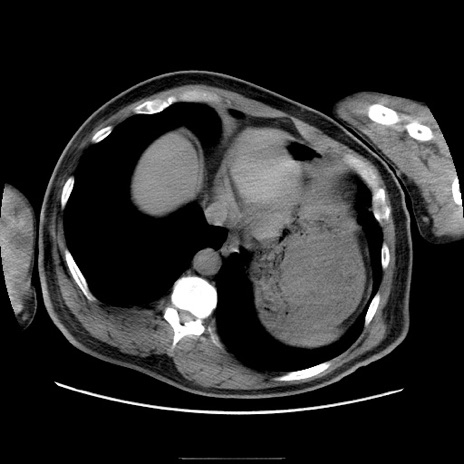

症例22(横断像)

【症例】50歳代男性

【主訴】腹痛

【現病歴】AVMからの被殻出血のため回復期リハ病棟入院中。 本日午後3時頃急に下腹部痛が出現した。

【既往歴】AVM、被殻出血、虫垂炎、高血圧

【身体所見】意識晴明、左半身不全麻痺、会話の理解は良好、36.5°C、腹部:膨隆、全体に板状硬、下腹部正中に圧痛点あり、反跳痛-、筋性防御不明、右下腹部にope scar

【データ】WBC 9400、CRP 0.06